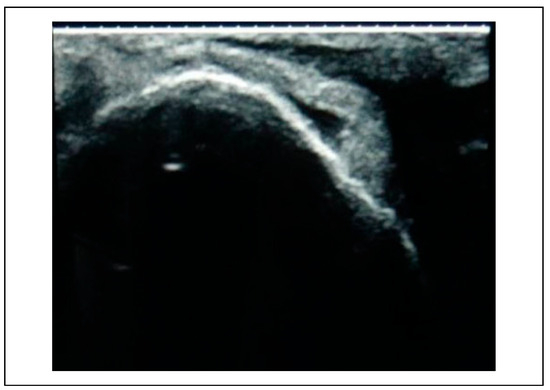

Figure 3.

Preoperative USG—infraorbital rim.

The subjects of the study group underwent an ultrasonographic examination before reduction at the frontozygomatic region, infraorbital rim and zygomatic buttress to assess the discontinuity of the bony fractured margins which were surface marked using a dermi marker at the respective points (Figure 3, Figure 4, Figure 5). These points served as landmarks to assess the reduction of the fracture site post reduction and fixation.